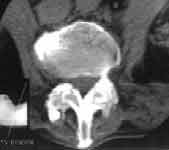

Осссификация передней продольной связки (Рис. 2.), а так же фиброзного кольца сочетается с остеопорозом тел позвонков (в первую очередь губчатой ткани). Иногда может отмечаться столь выраженная деминерализация, что тело позвонка становится даже менее плотным, чем межпозвонковый диск.

Рис. 2. РКТ поясничного отдела позвоночника. Оссификация правой боковой продольной связки и признаки анкилозирования межпозвонковых суставов.